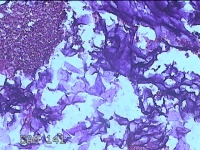

右侧颜面部结节

性别

男

年龄

35岁

临床诊断

皮脂腺囊肿

一般病史

发现右侧颜面部结节9个月余,无明显疼痛及不适。

标本名称

大体所见

灰白暗红色带皮肤样结节3x2x0.8cm一堆,表面糜烂。